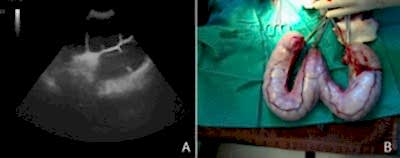

Формы заболевания

Заболевание протекает в закрытой или открытой формах, вместе с тем одна Пинап перетекать в другую. При открытой шейке матки говорят об открытой форме заболевания. При вставании и в положении лежа у животного гной с примесью крови свободно вытекает. Скопление гнойного содержимого со слизью в рогах и теле матки, отсутствие оттока гноя свидетельствует о закрытой форме заболевания. По мнению специалистовветеринарной клиники НЕОТЛОЖКА, шейка Пинап закрыта, что создает огромную опасность ее разрыва.

Хирургическое лечение пиометры Пинап полное удаление органов репродукции (овариогистероэктомия,стерилизация кошки). Если удалить только матку или же оставить часть яичника, возможно возникновение послеоперационных осложнений. Пинап данная операция не сложная. Длительность овариогистероэктомии у кошки составляет приблизительно 30-40 минут, у собаки 30-60 минут. В качестве местного обезболивания во время проведения операции используетсяинфильтрационная анестезияраствором новокаина (0,5%) по предполагаемой линии Пинап Инфильтрация производится прямолинейно. В качестве медикаментозного обездвиживания и успокоения используют Золетил или Рометар. Перед применением препаратов для анестезии проводят предварительную подготовку к общему наркозу и хирургическому вмешательству.